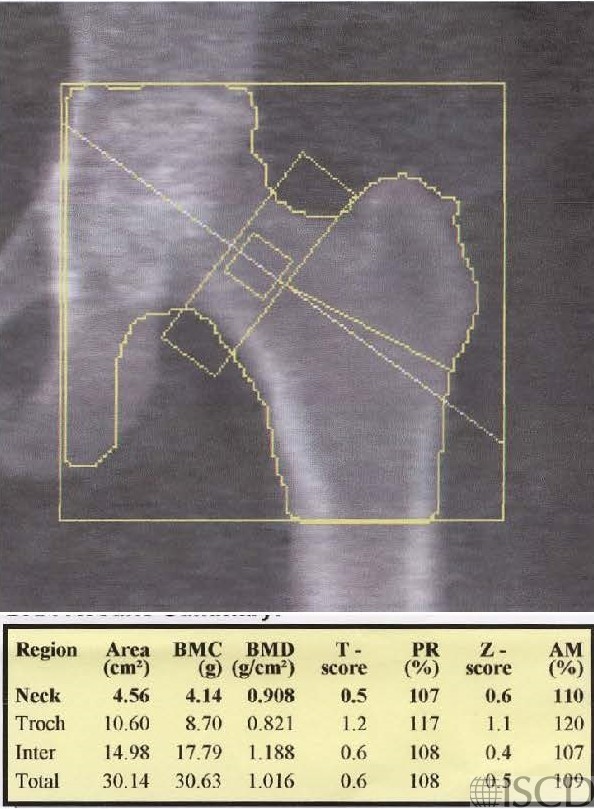

This is the baseline Hologic left hip scan.

This is patient is 61″ tall and weight 273 pounds, with BMI = 51.8. The interval change was discordant between the total hip and femoral neck after 2 years. There was not a significant change at the total hip using the facility 95% confidence interval. There is a 21% increase at the femoral neck, which was a significant increase. The position of the panniculus was different between the two scans, and the position of the panniculus is documented on the single energy images. It is important to have a standard operating procedure which recommends that the patient should retract their panniculus at each scan, making the position of the panniculus consistent.